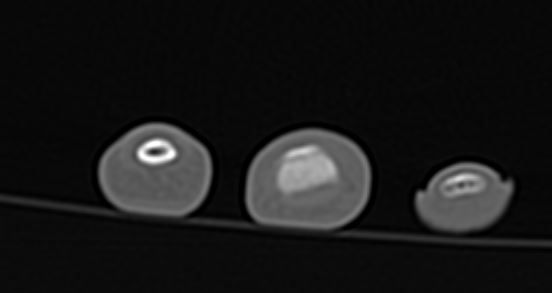

2주전 좌측 3,4수지 손가락이 바깥쪽으로 꺽였습니다.(CT&MRI 사진첨부 했습니다.)

증상은 좌측 제3수지 중지골에 피멍과 통증 그리고 손가락이 안으로 안굽혀 집니다.

골절인지 인대파열인지 아니면 다른 부분이 혹시 보이는지 알려주시면 감사하겠습니다.

• 4번 째 사진

volar plate라는 부분 손상이 의심되기는 하나 이게 명확한 진단은 아니네요. 이런경우는 정형외과 선생님의 임상 진단과 같이 결부해서 골절에 준해서 치료를 어떻게 할지 결정하게 됩니다. 필요하면 손가락 splint 착용하면서 경과를 보실 수 있으니 병원 진료대로 따라 가심이 좋겠습니다.